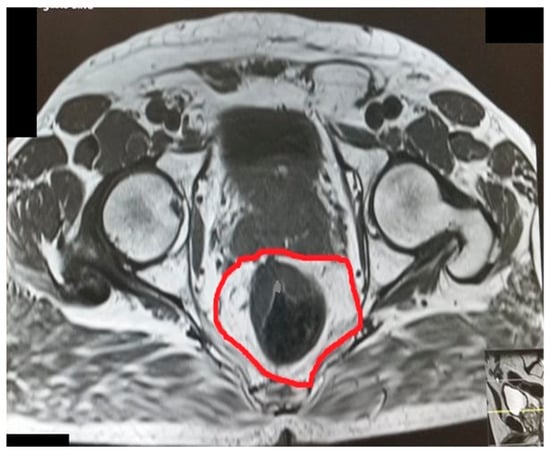

Interspinous distance.

Figure 5.